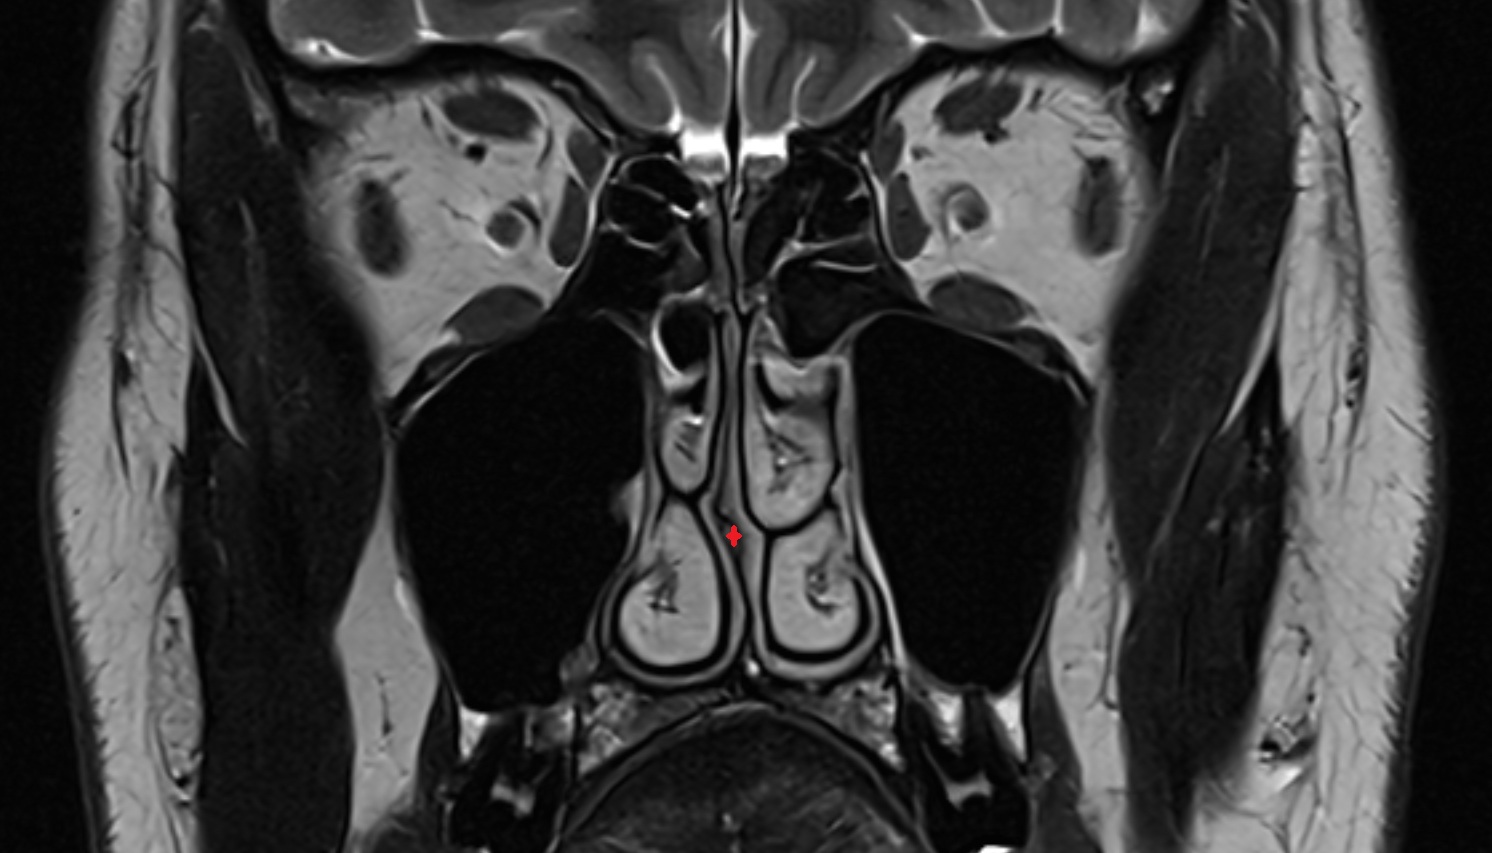

- Hippocampal head

- Hippocampal body

- Hippocampal tail

- Hippocampus